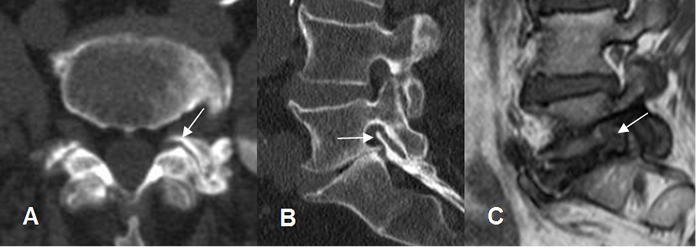

Fig 53. Canal estrecho central mixto.

A: TAC axial en ventana de tejido, B: TAC axial en ventana osea y TAC reconstrucción sagital. Canal estrecho mixto, con prominencia del disco, el cual está calcificado. (Flechas delgadas) y osteofito en la parte medial de la lámina derecha, que comprime el saco dural. (Flecha gruesa).